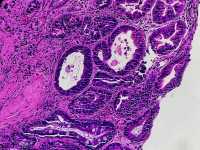

男66岁胃窦剥脱样糜烂

慢性萎缩性胃炎伴肠化、糜烂。可见修复性改变。